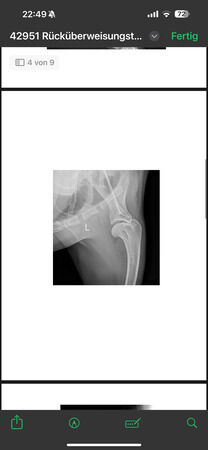

steht vorne sehr breit/ O-beinig, hi. re. Mitte Unterschenkel amputiert,

Knie li. deutlich verdickt, aber keine deutliche Instabilität.Verdickung hauptsächlich am

Oateöllasehnenansatz

radiologisch kein Kniegelenkserguß oder Arthrose, nur Weichteilschwellung im Bereich distaler

Patellasehne, Elle proximal verdickt und Fehlstellung (alte, verheilte Fraktur?), keine deutlich

Ellbogenarthrose, leichtgradige Fehlstellung Unterarm li., auch leichtgradige Fehlstellung Radius re.

Alle Gelenke sonst ohne deutliche Arthrosezeichen.